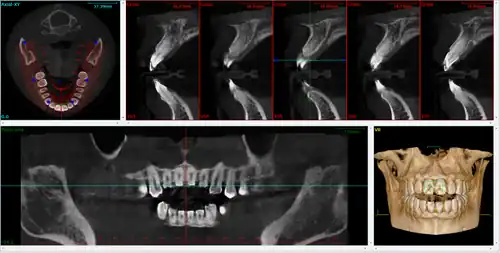

Implantology

A dental cone beam scan offers useful information when it comes to the assessment and planning of surgical implants. The American Academy of Oral and Maxillofacial Radiology (AAOMR) suggests cone-beam CT as the preferred method for presurgical assessment of dental implant sites.[20]

Orthodontics

As a 3D rendition, CBCT offers an undistorted view of the dentition that can be used to accurately visualize both erupted and non-erupted teeth, tooth root orientation and anomalous structures, that conventional 2D radiography cannot.[21]